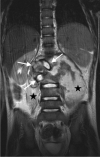

Tuberculosis (TB) remains one of the major public health threats worldwide, despite improved diagnostic and therapeutic methods. Tuberculosis is one of the main causes of infectious disease in the chest and is associated with substantial morbidity and mortality in paediatric populations, particularly in low- and middle-income countries. Due to the difficulty in obtaining microbiological confirmation of pulmonary TB in children, diagnosis often relies on a combination of clinical and radiological findings. The early diagnosis of central nervous system TB is challenging with presumptive diagnosis heavily reliant on imaging. Brain infection can present as a diffuse exudative basal leptomeningitis or as localised disease (tuberculoma, abscess, cerebritis). Spinal TB may present as radiculomyelitis, spinal tuberculoma or abscess or epidural phlegmon. Musculoskeletal manifestation accounts for 10% of extrapulmonary presentations but is easily overlooked with its insidious clinical course and non-specific imaging findings. Common musculoskeletal manifestations of TB include spondylitis, arthritis and osteomyelitis, while tenosynovitis and bursitis are less common. Abdominal TB presents with a triad of pain, fever and weight loss. Abdominal TB may occur in various forms, as tuberculous lymphadenopathy or peritoneal, gastrointestinal or visceral TB. Chest radiographs should be performed, as approximately 15% to 25% of children with abdominal TB have concomitant pulmonary infection. Urogenital TB is rare in children. This article will review the classic radiological findings in childhood TB in each of the major systems in order of clinical prevalence, namely chest, central nervous system, spine, musculoskeletal, abdomen and genitourinary system.